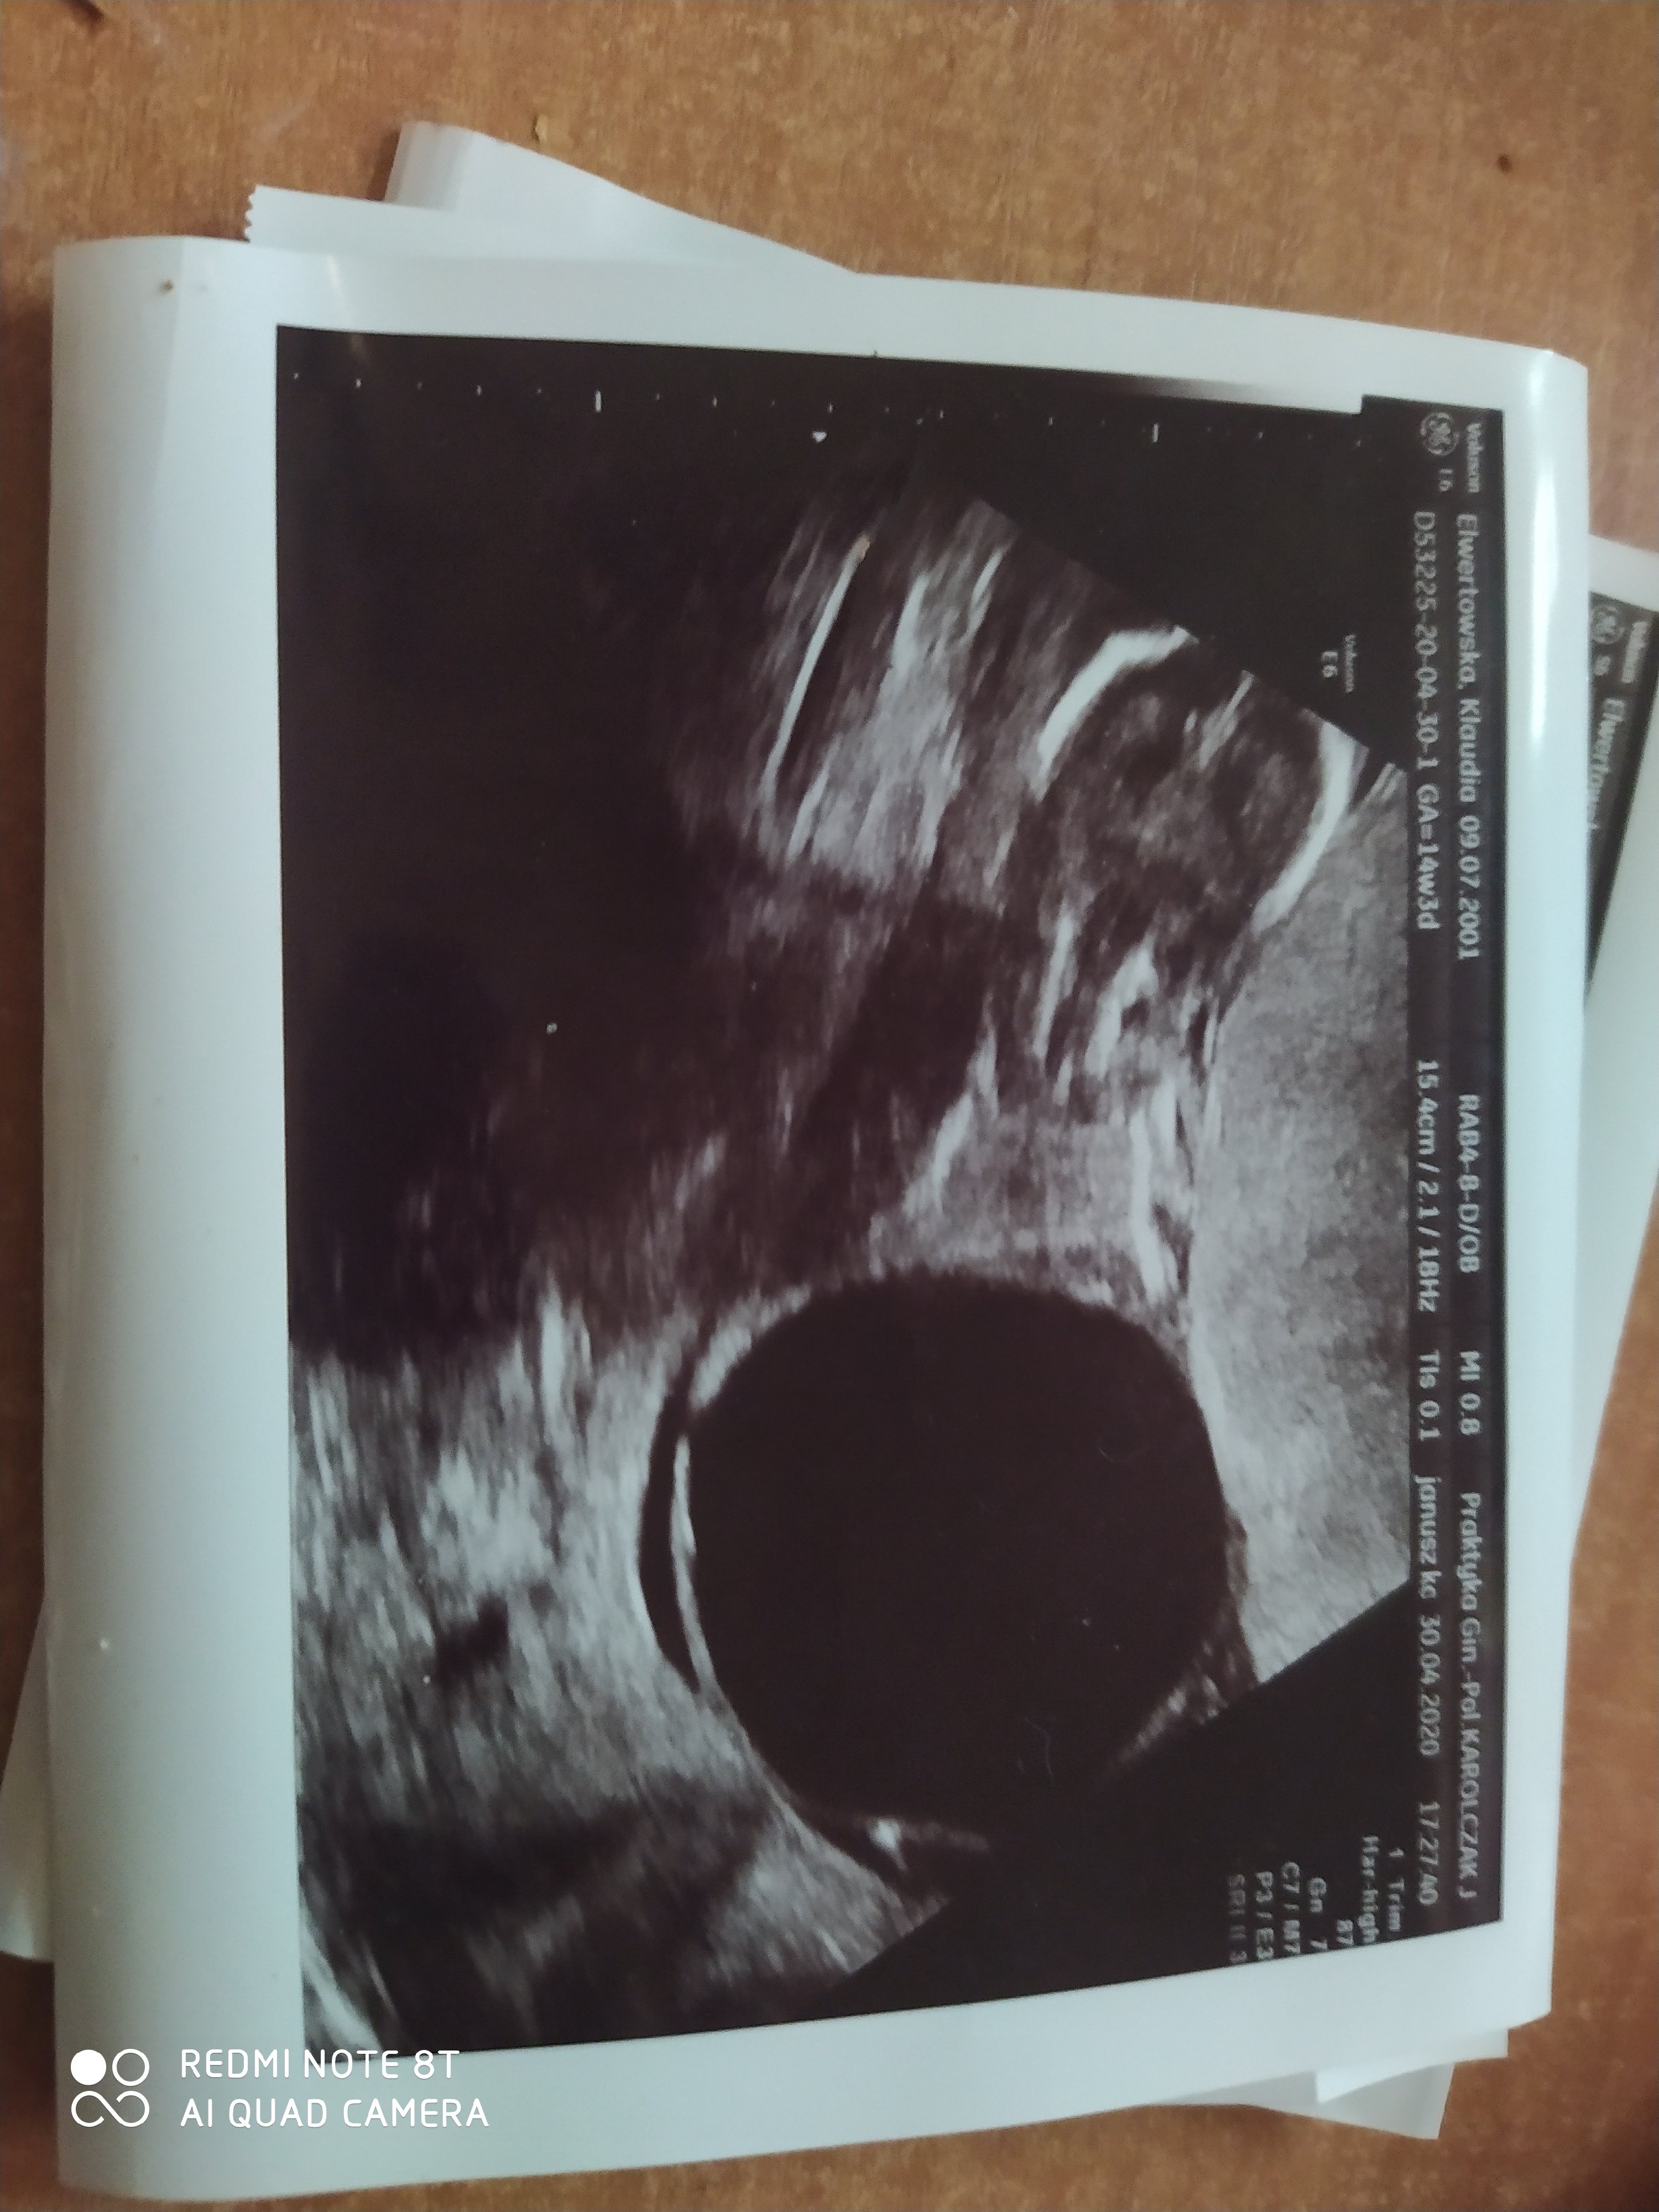

Czarna plama obok dziecka

Witam mam pytanie na ostatnim USG w marcu nic nie było a wczoraj na USG czarna plama co to może być lekarz prywatny twierdzi że to wada genetyczna miała jakaś dziewczyna takie cos

Szczerze to całe zdjecie jest dziwne bo ja na nim nie widzę dziecka a wywnioskowałam, ze jestes w 14 tc. Powinno być widać małego człowieczka. No chyba, że jest za tą wielką plamą. Na krwiaka to trochę za duże i za bardzo regularny kształt. A lekarz nic nie zasugerował, nie dał skierowania na dodatkowe badania? A jaki wynik był na badaniach prenatalnych?

Na badanie prenatalne idę w poniedziałek, niestety ginekolog prywatny nie powiedział co to jest powiedział tylko że to może być wada genetyczna i muszę to sprawdzić i to tylko tyle wziął 180 zł powiedział że mam się nastawić na najgorsze i to tyle ehh muszę czekać do poniedziałku

To cale usg jest jakieś dziwne, nie wydaje mi się że coś takiego może być wada genetyczna.. Prędzej bym powiedziała, że wadę to ma ale jego sprzęt